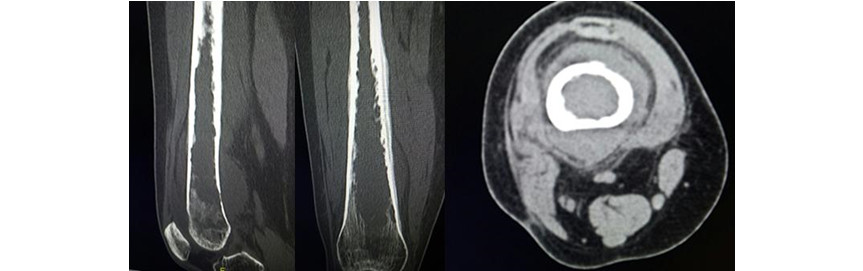

En la tomografía axial computarizada (TAC) del muslo derecho (Fig. 3) se observaron -en los planos sagital, coronaly axial- una masa de aspecto heterogéneo y densidad de 150 UH (que invadía extensamente el canal medular), osteolisis y periostitis en lámina de cebolla, y aumento de volumen de las partes blandas.

Fig. 3 - Tomografía axial computarizada del muslo derecho en planos sagital, coronal y axial. Obsérvense la masa heterogénea que invade el canal medular, osteolisis y periostitis.